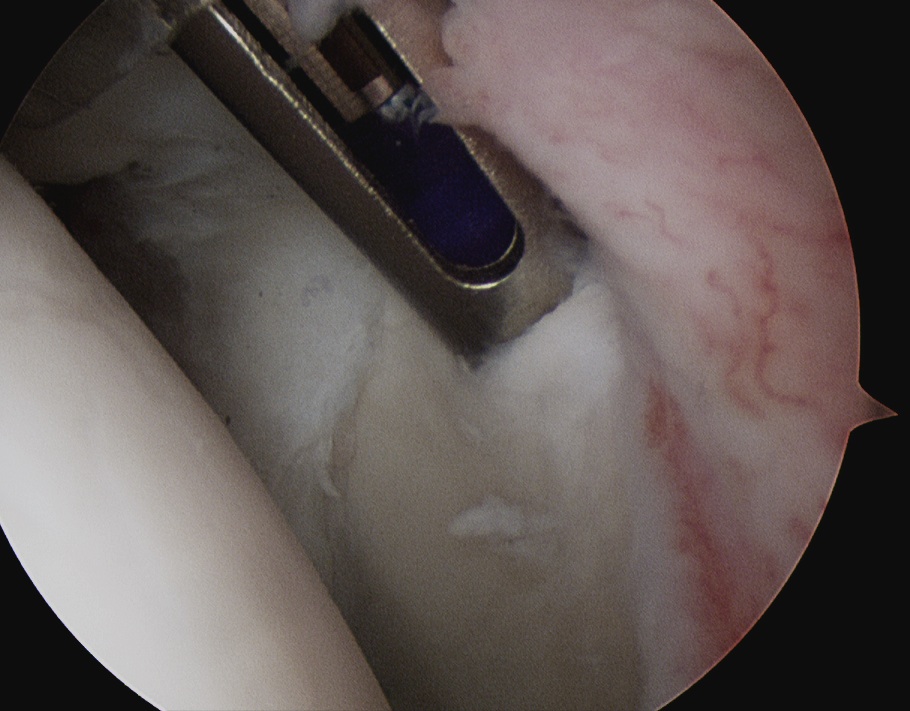

3. Anchors

Drill and insert via Wilminton portal

Usually 3 anchors is a minimum

Technique

- insert anchor

- suture through each cannula

- limb through W portal will be the suture limb that is passed

- suture passer through anterior portal (right angled for left shoulder)